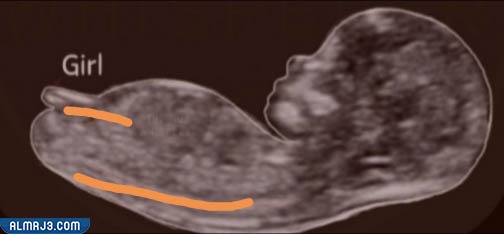

سونار البنت في الشهر الثالث

لمعرفة جنس الجنين بالاعتماد على نظرية النب ثيوري، لا بد أولًا من الحصول على صورة واضحة، لجسم الطفل، ومن ثم إيجاد النتوء التناسلي للطفل، والمعروف علميًا بمصطلح (Nub)، وذلك من خلال النظر، إلى مكان تكون ساقي الطفل، بعد ذلك تتم دراسة الزاوية، بين هذا النتوء والعمود الفقري، فإن كان هذا النتوء متجهًا للأسفل، بزاوية أقل من 30 درجة بالنسبة للعمود الفقري، فمن المتوقع أن يكون الجنين فتاة، وفي هذه الحالة، يكون النتوء التناسلي أفقيًا أكثر، بالنسبة لجسم الطفل، وبشكل يميل إلى موازاة العمود الفقري[4]، كما يظهر في صورة السونار الآتية: